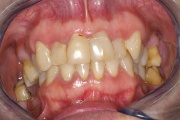

Kõige tavalisem kaebus sülje hüpofunktsiooni korral on püsiv, terve päev kestev suukuivus. Selline seisund nõuab sagedat joomist. Inimesed ärkavad tihti keset öö ja on sunnitud võtma klaasi vett endaga voodisse. Tuleb eristada aga neid, kes ärkavad põhiliselt hommikul, sest suukuivuse Loe edasi »